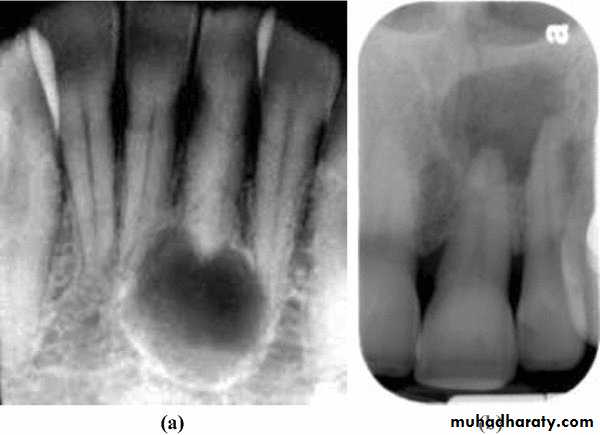

.” Periapical pocket cysts and periapical true cysts cannot be differentiated clinically or radiographically from other periapical conditions that manifest as radiolucencies. In the past, many practitioners have erroneously thought that well-defined borders of the radiolucency indicated a cyst but this is only indicative of a slowly developing lesion. A diffuse border is more likely to indicate a rapidly developing lesion. Likewise, the size of the radiolucency is not indicative of a cyst if it is large—since apical periodontitis, abscesses and cysts can be small or large. A large radiolucency is more likely to indicate a long-standing problem. Periapical pocket cysts cannot be diagnosed clinically and can only be diagnosed histologically. However, clinicians should recognize that this condition does occur and it should be part of the differential diagnosis of a persistent radiolucency following endodontic treatment

Radiographic findings—caries may be seen if extensive enough; a periapical radiolucency is present; the radiolucency is persisting or may be increasing in size despite recent endodontic treatment; root canal filling or intracanal dressing evident.

The size of the radiolucency and the appearance of the borders are not specific diagnostic signs that can be used to diagnose a true cys and can only be diagnosed histologically. However, clinicians should recognize that this condition does occur and it should be part of the differential diagnosis of a persistent radiolucency following endodontic treatment.

Radiographic findings—the tooth has a restoration; the periapical radiolucency is smaller than it was preoperatively and immediately postoperatively but it is persisting following root canal treatment or endodontic surgery; a root canal filling is evident; a root-end root canal filling may be evident if there is a history of previous endodontic surgery.

Depending on the amount of calcified tissue lost, root resorption can be detected by periapical radiographs. However, in many cases, the condition can be disclosed only by histologic sections Osteoclasts and odontoclasts possess similar enzymatic properties and resorb their target tissues in a similar manner.